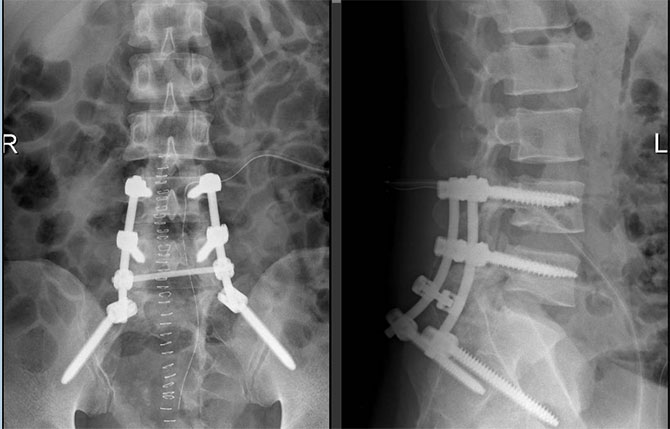

经过充分的术前准备,魏强主任医师领衔的泌尿外科团队与脊柱外科尹东主任医师团队携手,采用“前-后-前”联合入路打响“攻坚战”。首先行前路手术,在狭窄的盆腔深部分离肿瘤,发现肿瘤被上百条坚硬的韧带及致密结缔组织紧密包绕,犹如“钢筋铁骨”,分离难度极大,稍有不慎便可能损伤髂内大血管或输尿管。随后翻身行后路手术,这是整个手术的核心与难点:术者需在显微镜下于椎管内“抽丝剥茧”,仔细辨认并分离被肿瘤压迫、推挤的骶1、骶2、骶3神经根及马尾神经,在完整切除肿瘤的同时,力争保留每一根神经纤维。完成椎管内松解与腰骶部力学重建后,再次前路手术,最终将这颗重达3公斤的“巨型炸弹”分两块完整取出。魏强主任感叹:“这是我职业生涯中遇到的最大盆腔神经鞘瘤。”尹东主任也表示:“如此巨大的腰骶神经鞘瘤,在脊柱外科领域也极为罕见。”

术后转入ICU观察24小时后,黄先生生命体征平稳返回病房。在护理团队精心照护下,他恢复顺利,术后第3天即在腰围保护下下床活动,双下肢肌力及大小便功能完好无损。当黄先生看到病理报告上的“神经鞘瘤,切缘阴性”时,这位七尺男儿眼眶湿润,与年迈的父母向医护团队致谢。